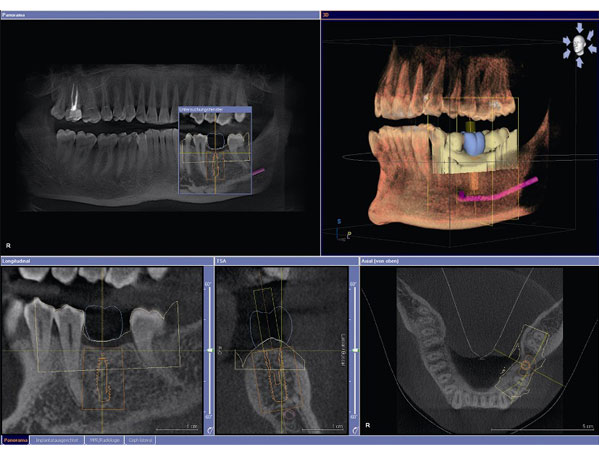

Clinical Impact: Enables sub-millimeter implant planning accuracy (0.12mm RMS error in 3D landmark studies) even with full-arch zirconia bridges present.

Contemporary CBCT systems (e.g., Planmeca ProMax®, Carestream CS 9600, Vatech PaX-i³D) have evolved beyond mere imaging devices to become workflow orchestrators. Critical integration pathways include:

| CAD/CAM Handoff | Native DICOM-to-STL conversion with calibrated voxel-to-mesh transformation; Anisotropic resolution compensation algorithms | ISO/ASTM 52900:2021, STEP AP 247 | 11.7 min eliminated per surgical guide case |

Seamless CBCT data flow into design environments is non-negotiable for precision outcomes. Current integration maturity:

| exocad DentalCAD® | Native DICOM importer (v4.2+); Direct scanner interface via exoplan API | • AI-driven bone density mapping • Implant planning with trabecular analysis • Real-time collision detection during guide design |

| 3Shape TRIOS Implant Studio | Proprietary CBCT SDK; Integrated with 3Shape X1 Scanner | • Dynamic bone quality simulation • Guided workflow with auto-occlusion transfer • FDA-cleared AI path planning (510(k) K250123) |

| DentalCAD (by Dessignare) | Open DICOM 3.0 interface; Python API for custom pipelines | • Multi-CBCT fusion (e.g., CBCT + MRI) • DICOM-RT dose simulation • ROS 2.0 robotics integration for surgical robots |